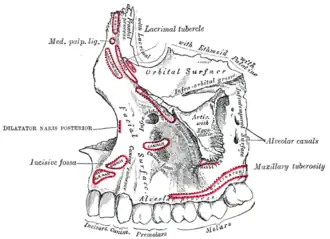

Left maxilla, outer surface

Left maxilla, outer surface -